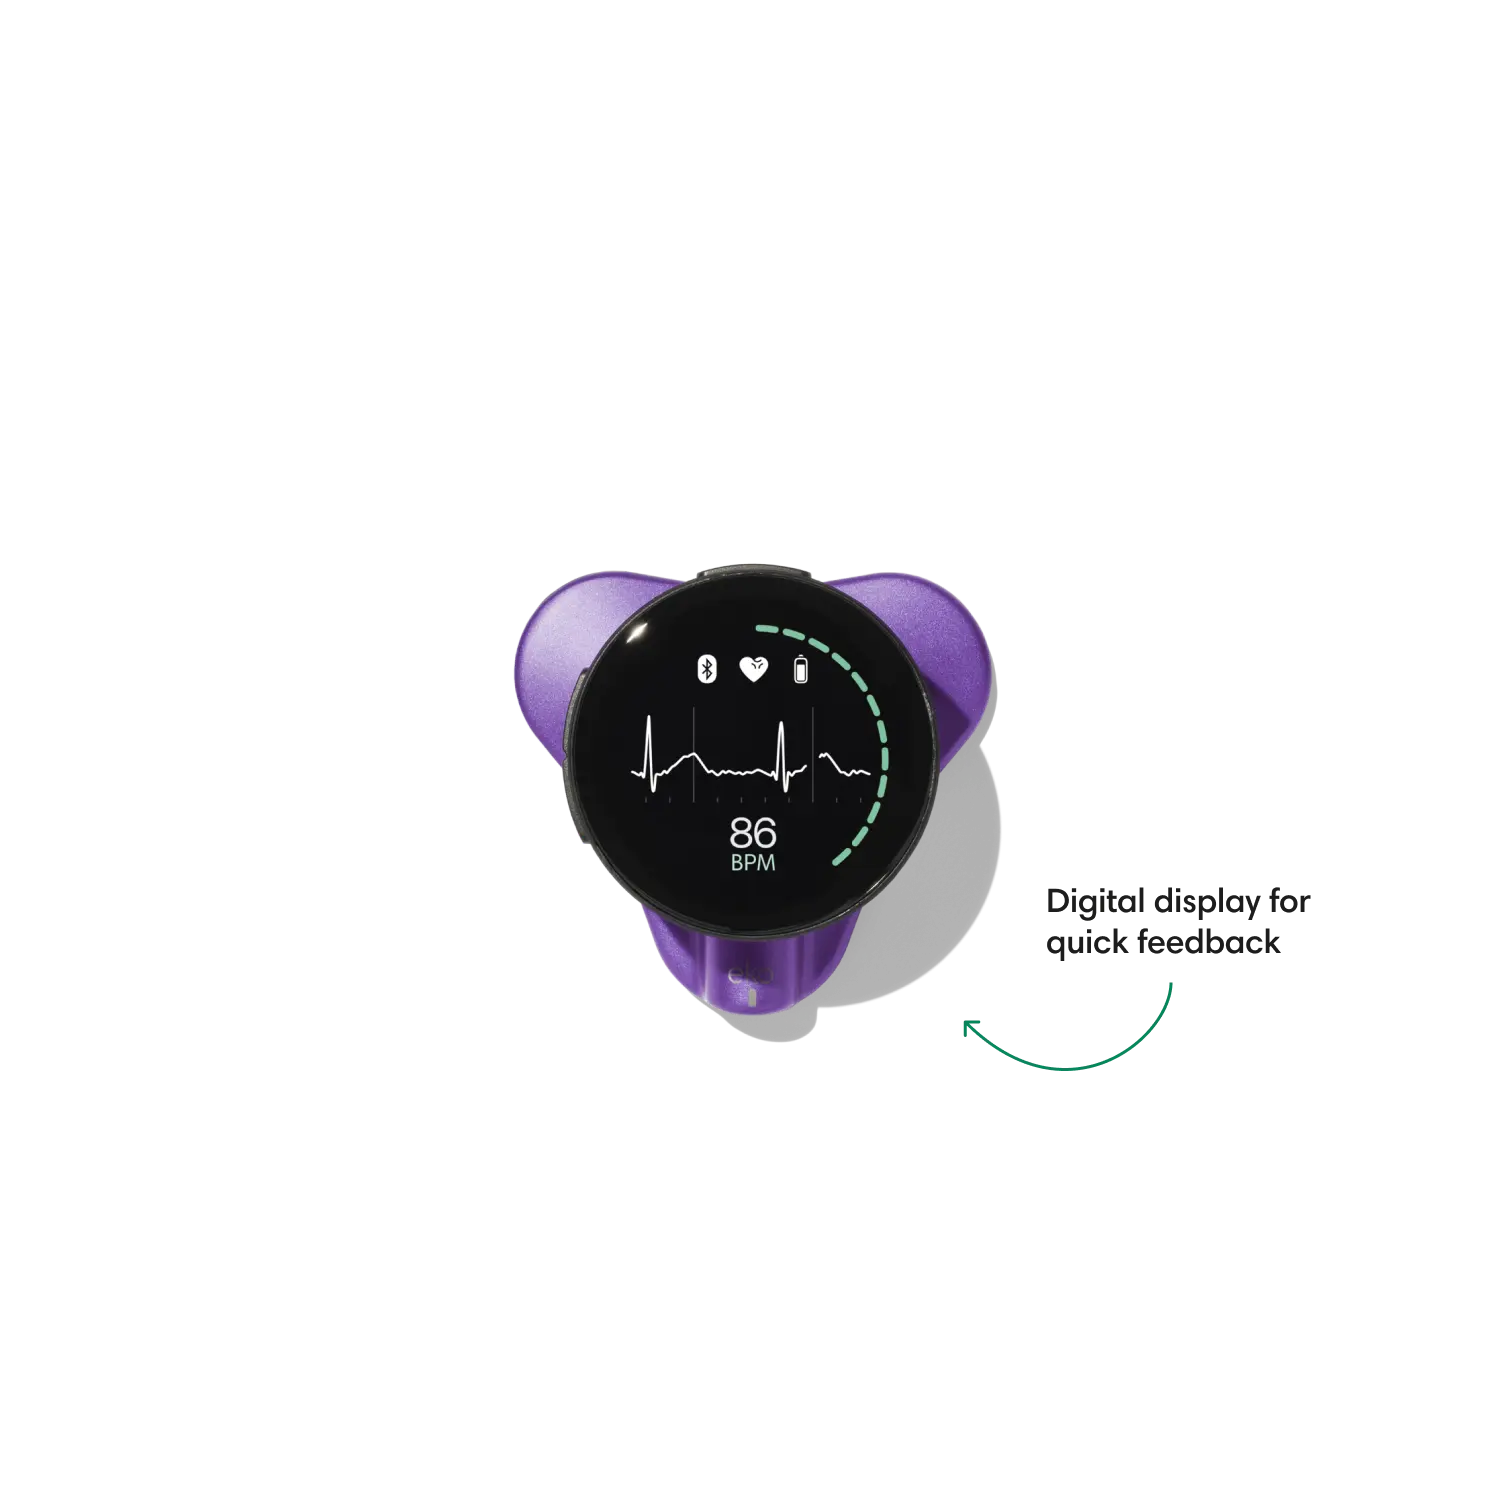

Go beyond sound alone.

For the first time ever, measure heart rate, visualize 3-lead ECG, and see detection results — right on a built-in, full-color display.